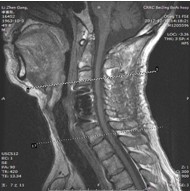

患者,男性,49岁,主因“行走不稳2个月伴右前臂麻木1个月”入院

2月前开始出现双下肢行走不稳,有踩棉花感,行走距离受限。1月前出现右侧前臂及手指麻木感。3周前诊断为“颈椎病”,保守治疗无改善,行走不稳症状加重

查体:右侧中指轻触觉、针刺觉减退,左侧上肢及双下肢感觉正常。

肌力:指屈肌群 左/右=5/4级,小指外展肌 左/右=5/4级。双侧膝腱反射亢进。双侧hoffman征阳性。肛门深感觉、自主肛门括约肌收缩存在。